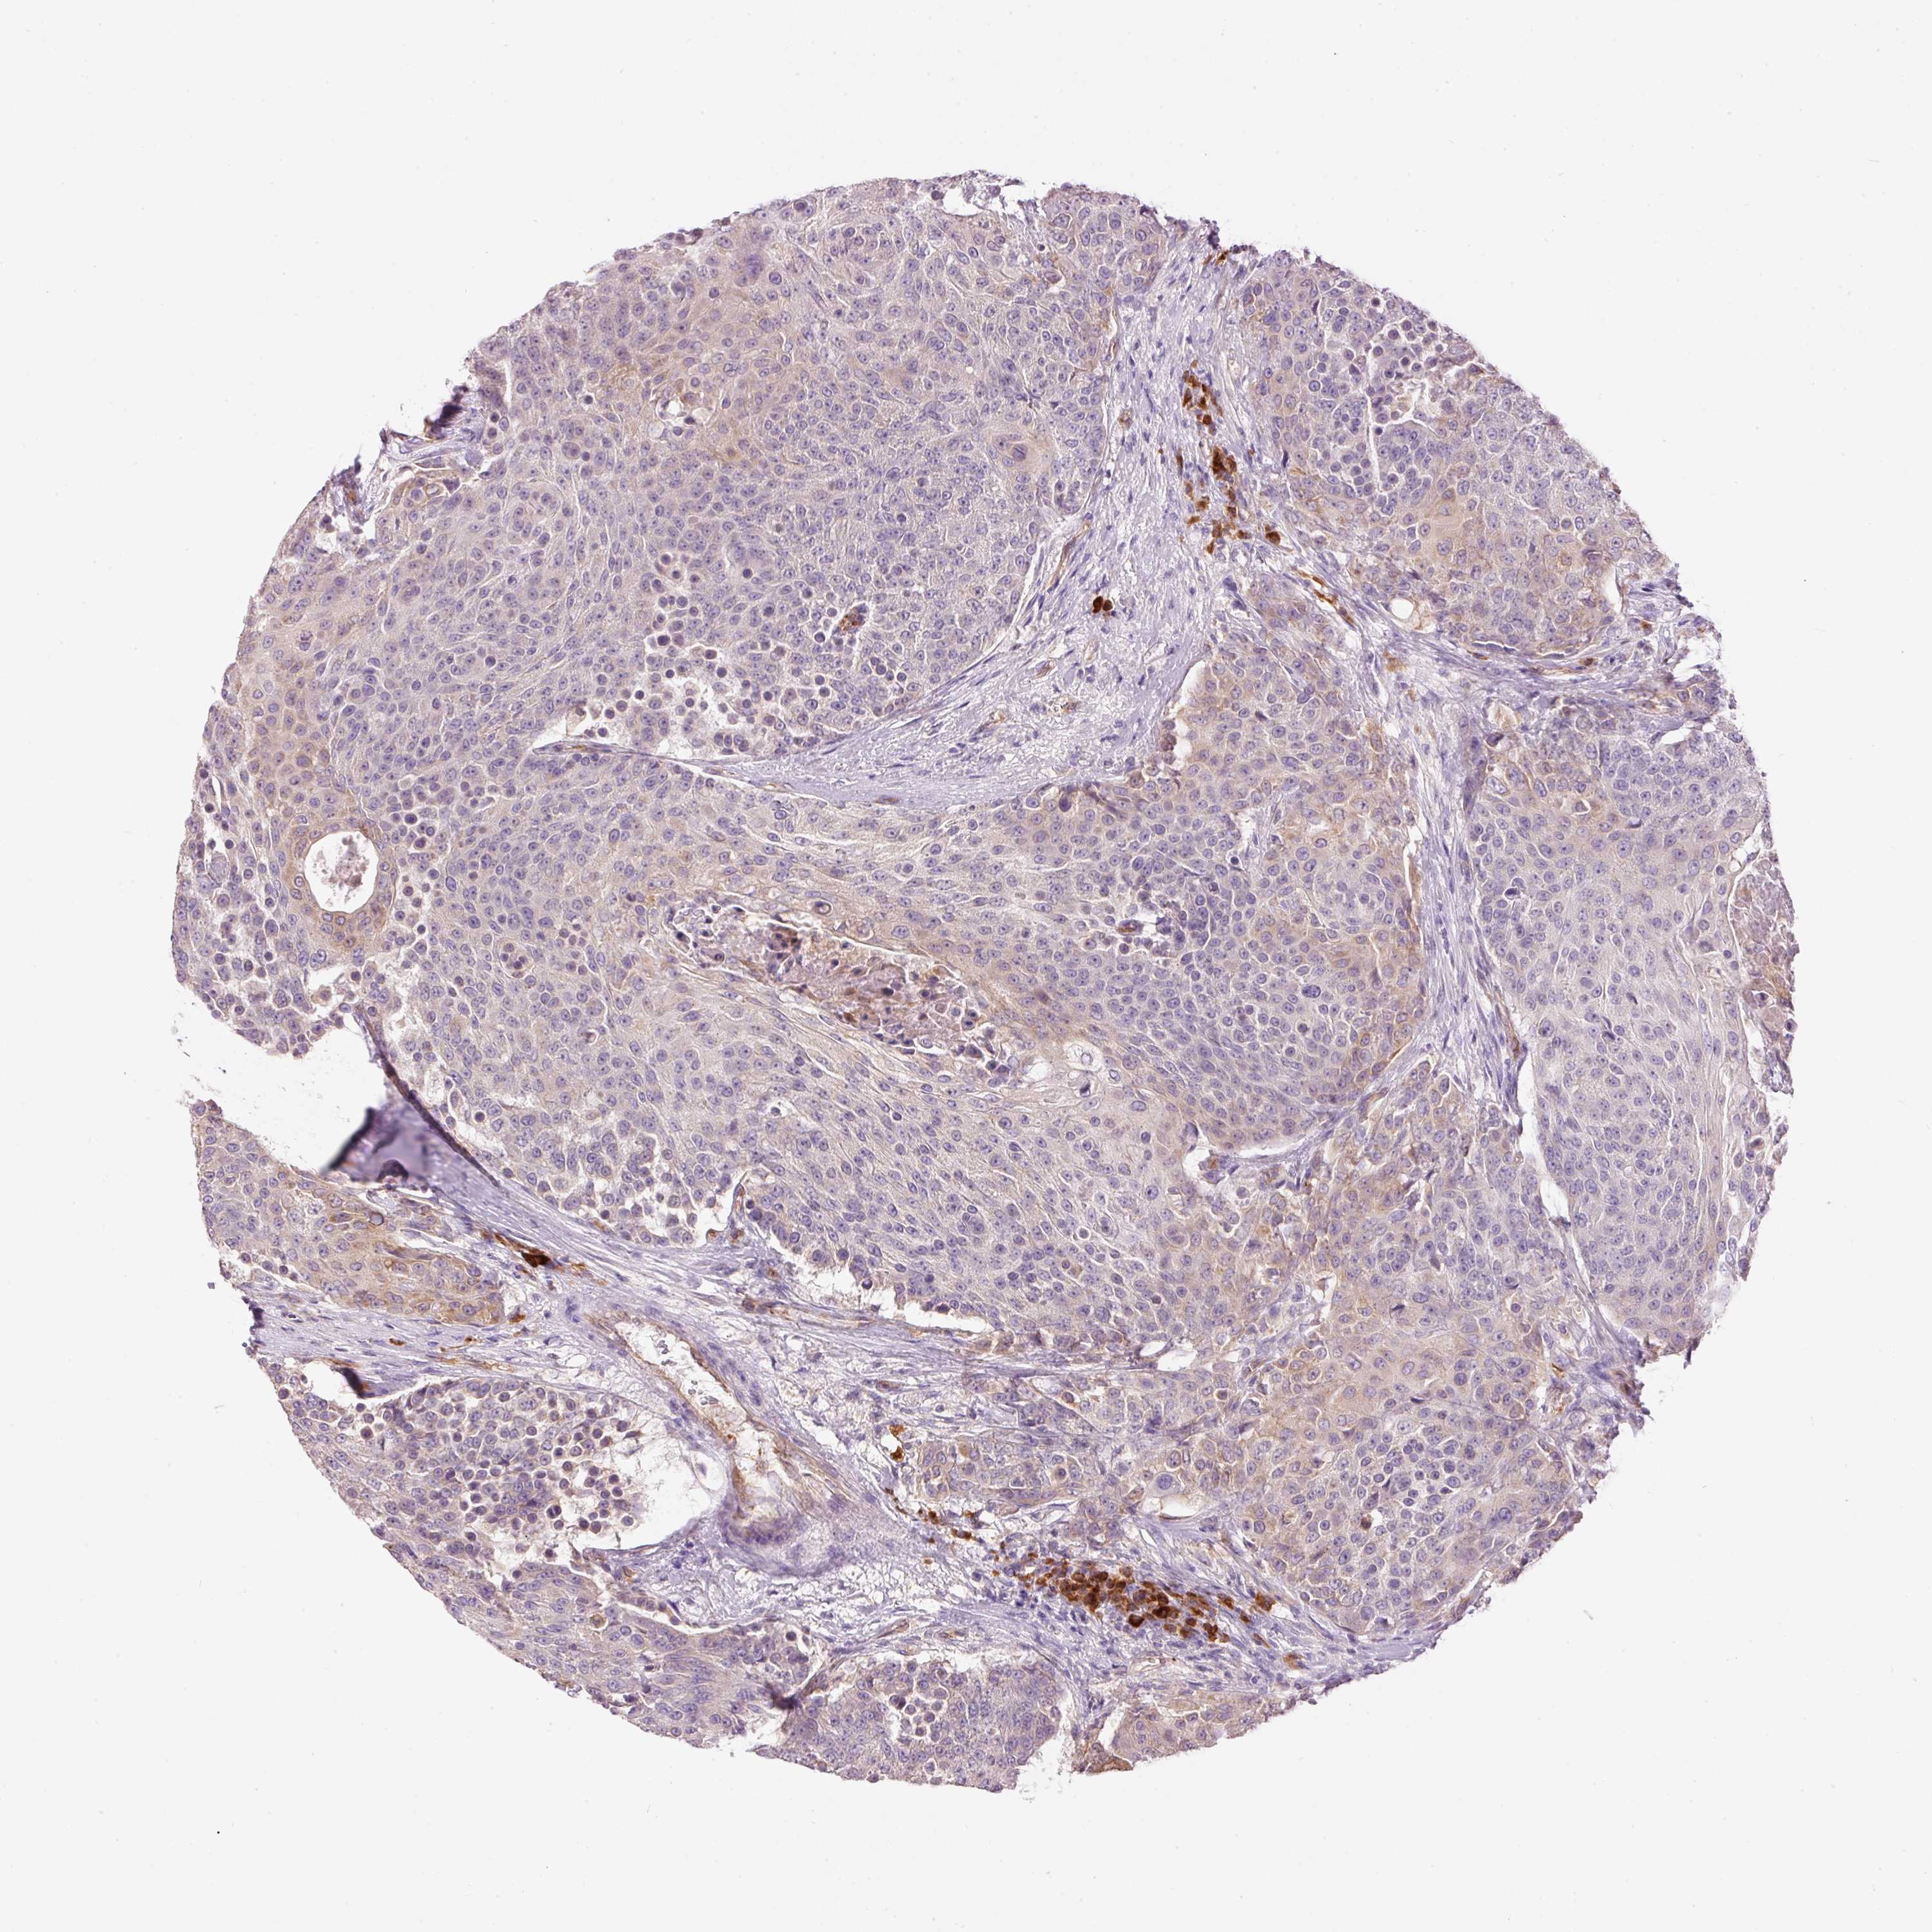

UROTHELIAL CANCER - Protein expressioni

A mouse-over function shows sample information and annotation data. Click on an image to view it in a full screen mode. Samples can be filtered based on level of antibody staining by selecting one or several of the following categories: high, medium, low and not detected. The assay and annotation is described here.

Antibody stainingi

Antibody staining in the annotated cell types in the current human tissue is reported as not detected, low, medium, or high, based on conventional immunohistochemistry profiling in selected tissues. This score is based on the combination of the staining intensity and fraction of stained cells.

Each image is clickable and will lead to virtual microscopy that enables deeper exploration of all samples and also displays staining intensity scores, fraction scores and subcellular localization as well as patient and tissue information for each sample.

Antibody HPA050409

Antibody HPA054211

Urothelial carcinoma, Low grade

Urothelial carcinoma, High grade

Urothelial carcinoma, NOS